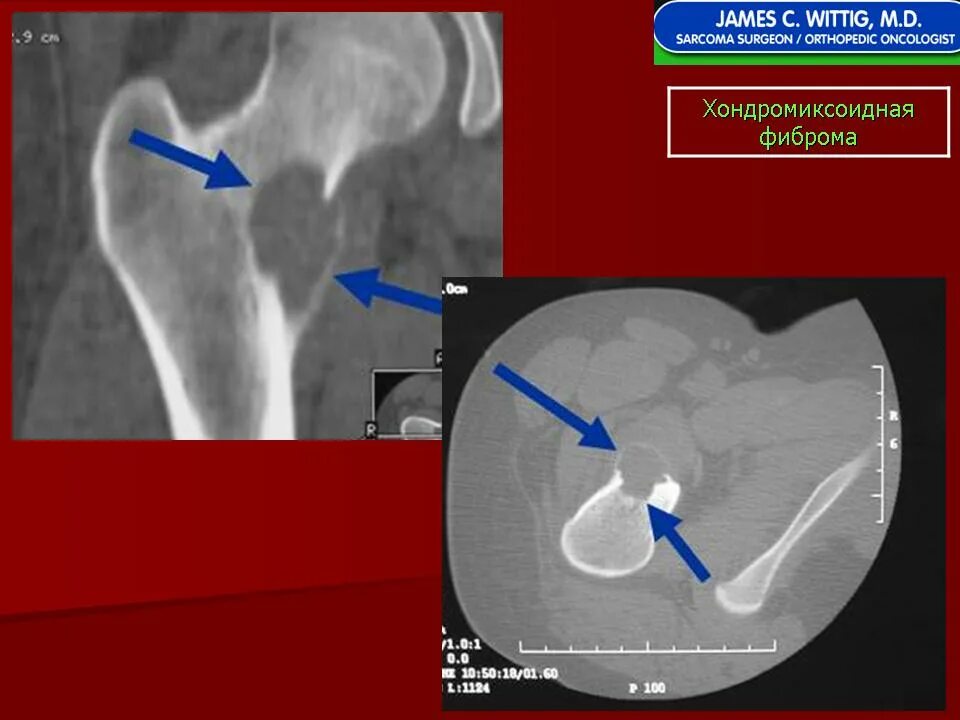

Фиброма кт